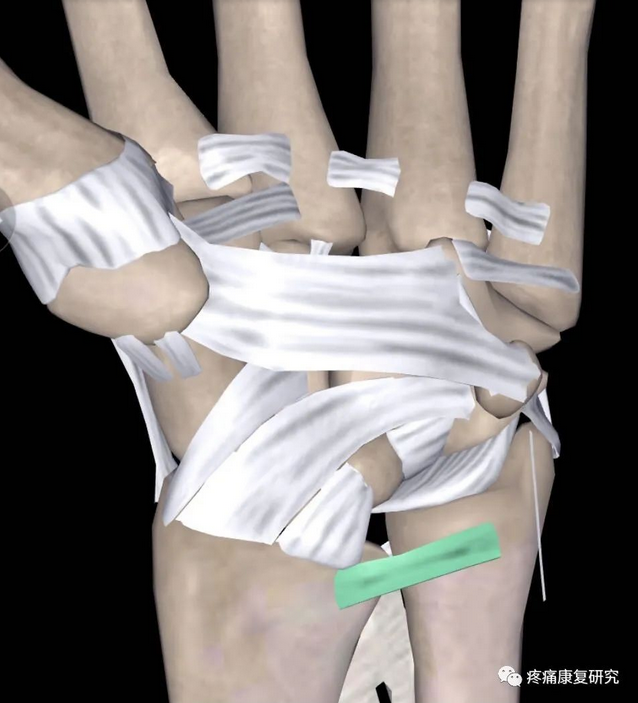

1.三角纤维软骨复合体(TFCC)

TFCC 组成包括三角纤维软骨(TFC)、半月板同系物、尺侧副韧带、桡尺远端掌背侧韧带、尺三角韧带、尺月韧带、尺侧腕屈肌腱鞘、桡尺三角韧带等,其中 TFC 是其主要结构。

TFCC 具有稳定下尺桡关节、传递轴向负荷、缓冲尺骨头对腕骨的撞击等作用。